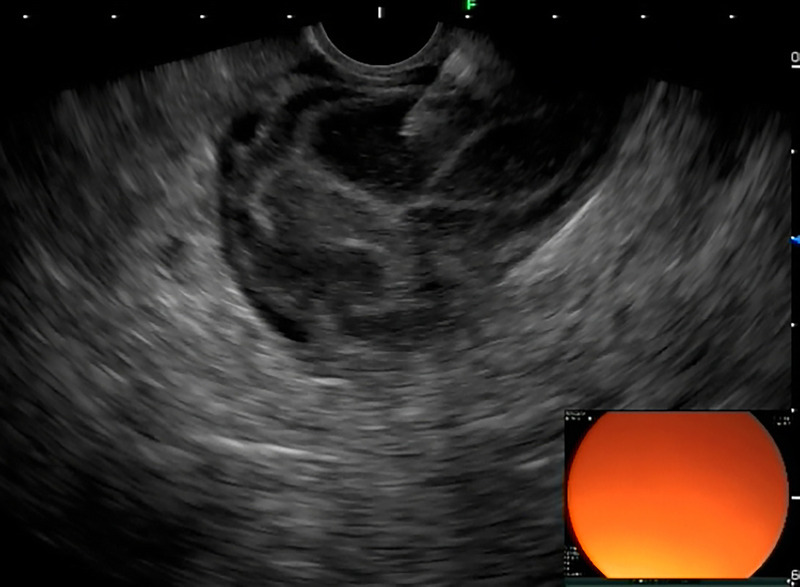

A rare but interesting case of small intestinal tumor diagnosed by transrectal EUS-FNA (with video).